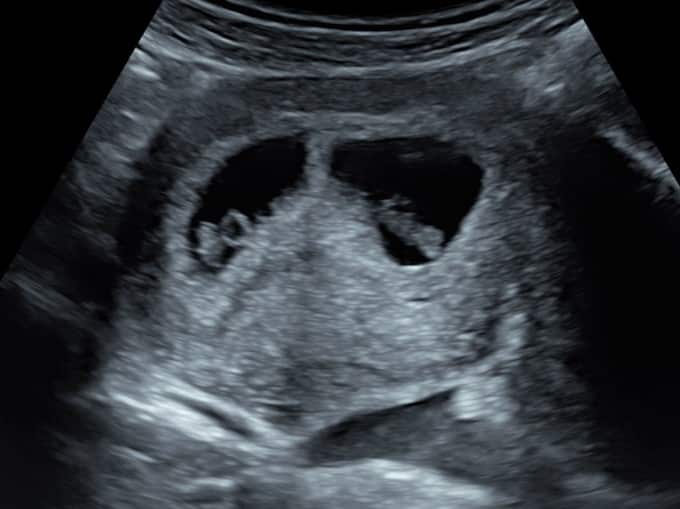

The first thing the sonographer looks for is the position of baby. They will check the baby is in the uterus as it should be, rather than elsewhere which can be dangerous for mum. The sonographer will then look for the number of pregnancy sacs and babies to confirm a single or multiple pregnancy. The heartbeat is next; during your early pregnancy scan we do not listen to the heartbeat as it wouldn’t be safe for baby, but we will show you the heartbeat flickering on our screens.

Once the heartbeat is confirmed, the sonographer will check the pelvic area and ovaries to make sure the area around baby is healthy. If you’re experiencing any worrying symptoms, our sonographer will be able to confirm the reasons why during this part of the scan.

Once the pelvic assessment is complete, the sonographer will return to your baby and measure their length from crown to rump (head to tail) to provide you with accurate dating.